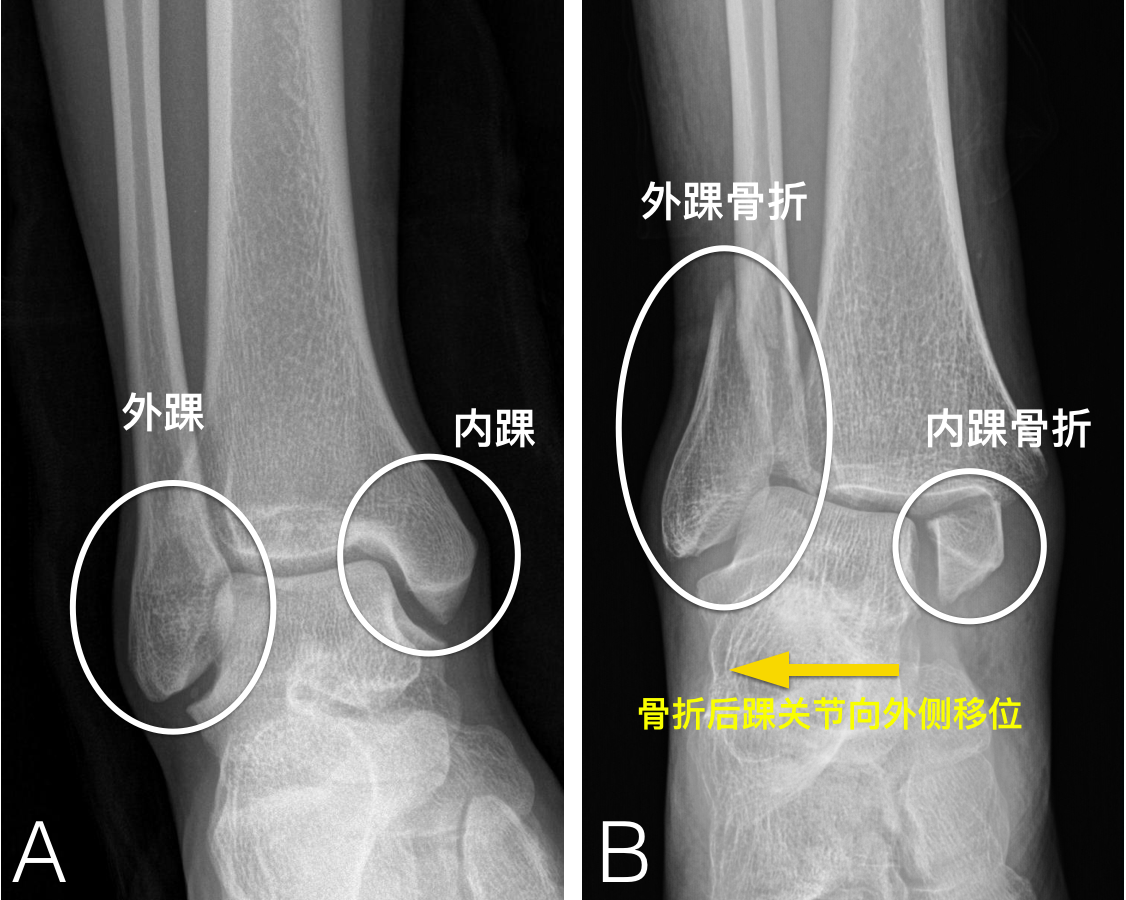

踝关节骨折及术后康复策略 踝部骨折 踝部骨折

案例分享 三踝骨折术后 康复实录 知乎